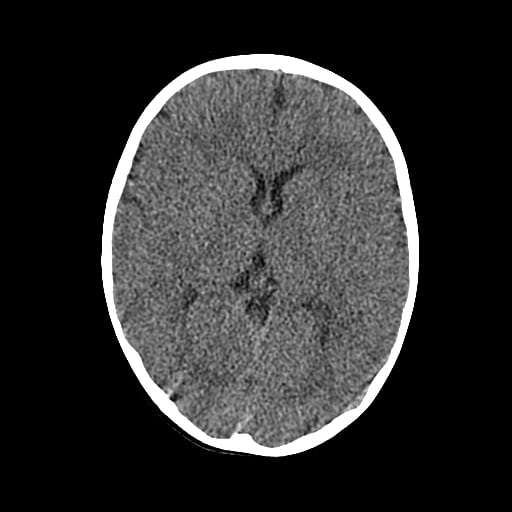

Age: 1

Sex: Male

Indication: Fall